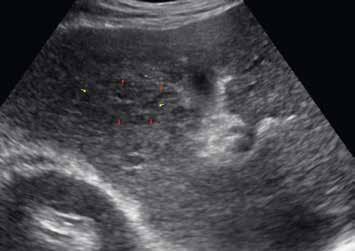

V UZ jsou patrná vícečetná izoechogenní ložiska (1, 2). U jiného pacienta (3) vidíme v játrech převážně hypoechogenní ložiska (žluté šipky) s naznačeným hyperechogenním periferním lemem (červené šipky). Po aplikaci kontrastní látky se ložiska patrná na obr. 1, 2 homogenně sytí a ani téměř po třech minutách nedochází k jejich vymývání (4–6).

Ultrazvukový obraz ukazuje většinou homogenní, někdy lobulované ložisko. V 60 % je hypoechogenní (obr. 1, 2), může však být izoechogenní nebo mírně hyperechogenní (obr. 3) vzhledem k normálnímu jaternímu parenchymu. Častěji se FNH vyskytuje v terénu steatotických jater. Ve 20 % případů nacházíme centrální jizvu.

V pravém laloku jater jsou na UZ lehce hypoechogenní ložiska s naznačeným výrazně hypoechogenním lemem (1, 2).

Na UZ je mezi kurzory patrné objemné nehomogenně hyperechogenní oválné ložisko (3).